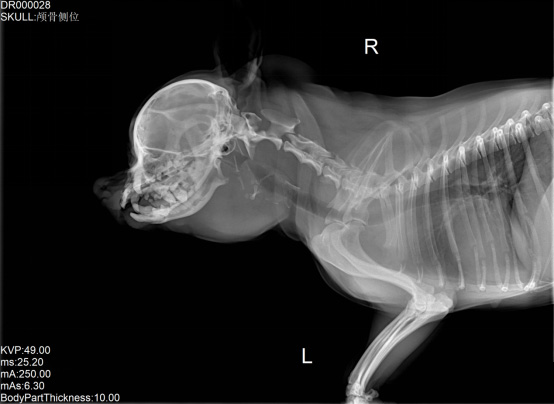

寵物DR是專業(yè)用于寵物X光拍攝的數(shù)字化X射線檢查,輔助寵物醫(yī)生進行及時精確的診療。寵物DR主要包括五大主要部件,數(shù)字X光探測器,高壓發(fā)生器,球管,機架,寵物專用的DR工作站軟件。寵物DR由于采用數(shù)字技術(shù),自動成像處理,模擬X線圖像向數(shù)字化X線圖像的轉(zhuǎn)變。寵物DR與傳統(tǒng)模擬X光機相比有什么優(yōu)勢呢?采集時間10毫秒以下,成像時間僅為3秒,較高的空間分辨力和低噪聲率,提高了病灶的檢出率,避免漏診誤診等問題。減少X線對人體照射的不良影響寵物DR照片是您最佳的選擇。提高寵物醫(yī)生工作效率,總而言之,選擇寵物DR是寵物醫(yī)院的最佳選擇。寵物醫(yī)學影像學實現(xiàn)全數(shù)字化和無膠片化升級發(fā)展提高技術(shù)水平。